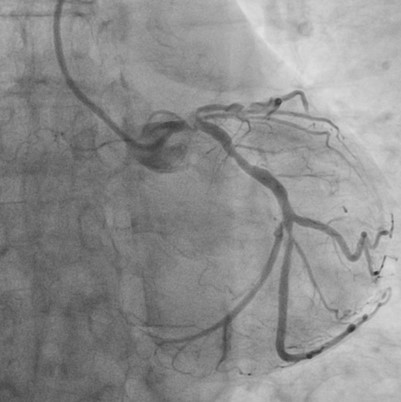

Relevant Catheterization Findings

Catheterization revealed a 95% distal left main stenosis with a calcified nodule protruding into the LAD and LCX ostia, a 99% proximal LAD lesion with an additional 90% stenosis after the first diagonal branch, non-critical LCX disease, and a 70% proximal RCA lesion with multiple critical PDA stenoses. The patient and family declined PCI in the cath lab, with a Syntax score of 40.